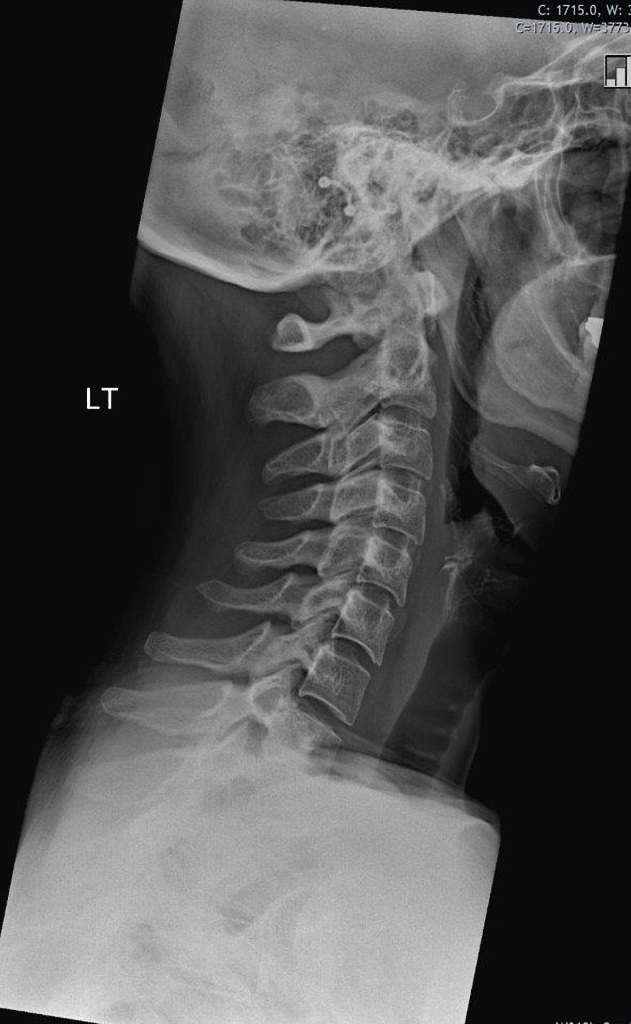

1.X-Ray:

It is easiest mean to image the spine.X-ray reveals alignment and degenerative changes of the bones.The spaces for the discs are seen as well, but no pictures are seen of the spinal cord,nerves or actual disc material. Unsuspected bony pathology, such as fractures,dislocations and cancer metastases, are quickly identified with X-ray.